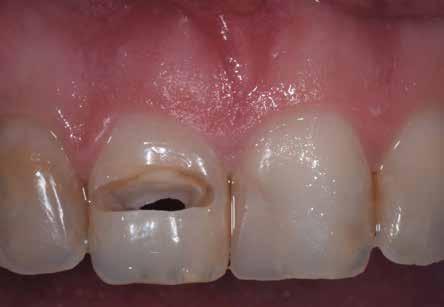

A korai harmicas éveiben járó hölgy rendelőnkbe érkezésének oka a jobb felső nagymetsző fog bizonytalan érzkenysége, elmondása alapján gyermekkorában trauma érte a felső frontrégiót. A frakturált klinikai koronákat kompozittöméssel helyreállították, egyéb kezelést akkor nem tartottak szükségesnek. Az utóbbi hónapokban tapasztalt érzékenység miatt kereste fel rendelőnket. A klinikai vizsgálat (1. és 2. kép) és a CBCT felvétel (3. kép) alapján diagnosztizált külső gyökérreszorpció megoldására a fog eltávolítását, implantátum

bukkális 1. kép: Kiindulási állapot, 2020. január. 3. kép: Kiindulási CBCT felvétel. 2. kép: Kiindulási állapot a palatinális oldal felől.